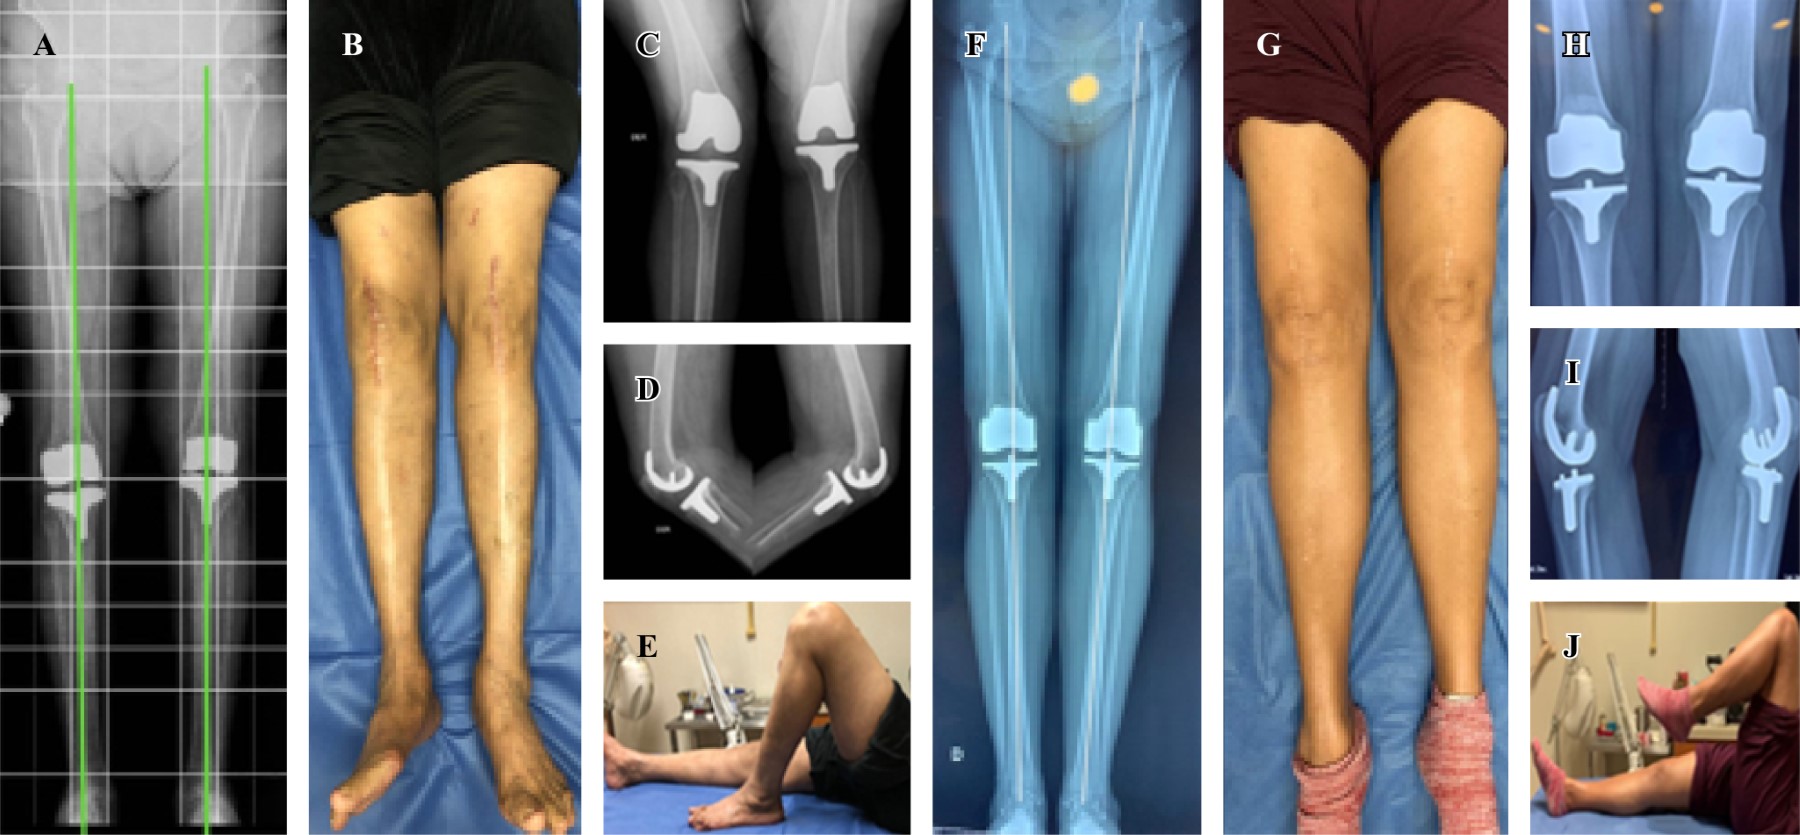

En relación al eje mecánico, 100% de los pacientes intervenidos tienen una desviación entre 0o y 2o en el plano coronal (Figura 1). La función con los resultados de la escala de WOMAC prequirúrgica y postquirúrgica mostró una media de 22.71 ± 3.34 prequirúrgica y 4.16 ± 1.84 postquirúrgica, con diferencias estadísticamente significativas p = 0.000 (IC 95% de 17.16 a 19.92) (Tabla 1).

En relación a la movilidad articular de flexoextensión bilateral obtenemos mejoría con diferencias clínicas significativas tanto derecha como izquierda con p < 0.05 (Tabla 1). Se muestra resultado clínico y eje mecánico radiográfico de cuatro pacientes a diferentes años postquirúrgicos (Figuras 2 y 3).